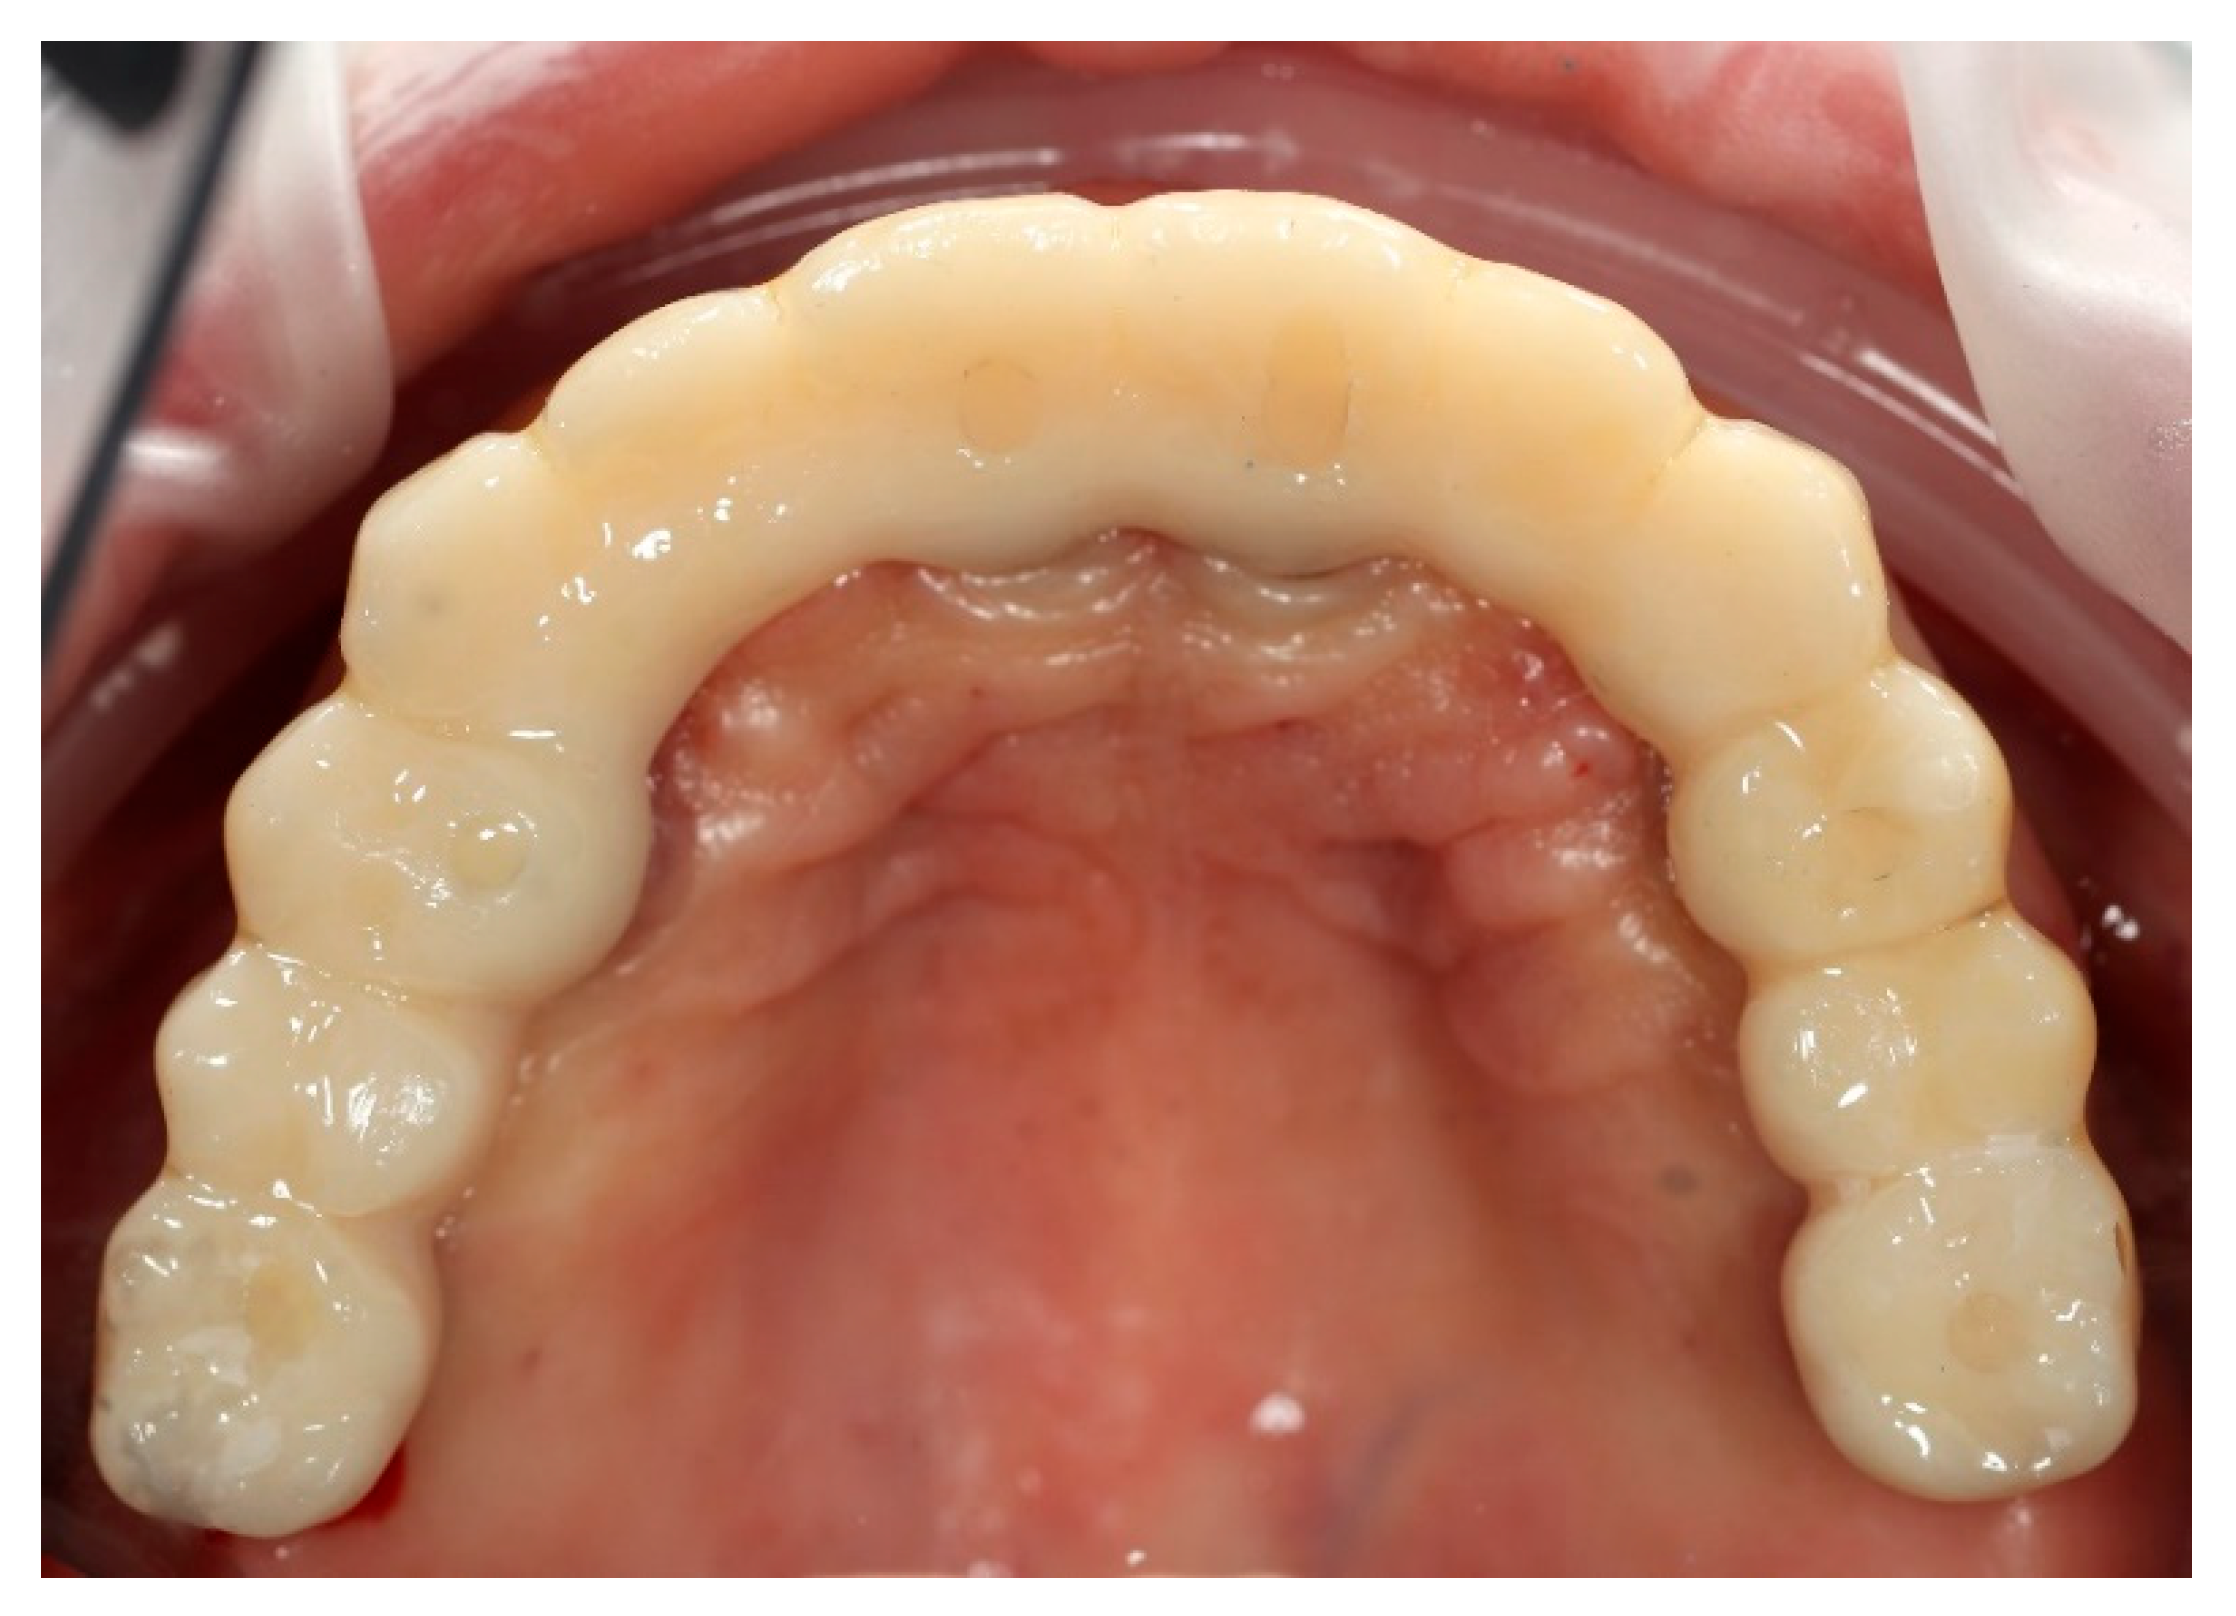

Figure 9. Digitally planned, 3D-printed full-arch provisional restoration delivered early and fixed to the multi-unit abutments with screws, shown in situ (occlusal view).

Based on the merged datasets (biocopy + SmartFlags® scan), the provisional screw-retained, implant-supported full-arch prosthesis was designed in Exocadsoftware (Exocad GmbH, Darmstadt, Germany) and subsequently fabricated using OnX Tough 2 resin (SprintRay Inc., Los Angeles, CA, USA) by means of 3D printing. The intaglio (tissue-facing) surface was polished [18], while the labial surface was characterised and glazed to improve aesthetics (Optiglaze Clear, GC International AG, Luzern, Switzerland). As demonstrated in the accompanying clinical photographs, minor superficial cracks in the glaze layer are visible on the external surface of the prosthesis (Figure 8).

Finally, the prosthesis was delivered by fixing to the multi-unit abutments with screws. Clinical adjustments were performed to ensure perfect fit, occlusion, phonetics, and aesthetics. The patient reported immediate improvement in comfort and satisfaction compared to the acrylic splint (Figure 9 and Figure 10).